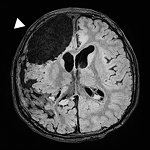

Cancer Discov.2025 Jul 3;15(7):1377-1391.

Distant origin of glioblastoma recurrence: neural stem cells in the subventricular zone serve as a source of tumor reconstruction after primary resection.

Mol Cancer.2025 Mar 4;24(1):64.